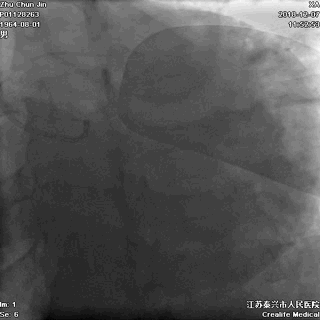

▲右冠不好找呀!

▲非选择性右冠造影,血管通着咧!

▲在主动脉根部推造影剂,似乎也看不出太多异常